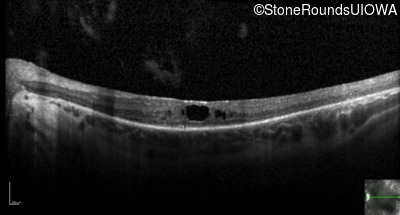

Optical Coherence Tomography - Right - 20/80 +2

Exemplar / OCT Stack